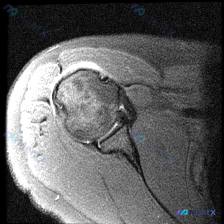

最近整理了一份肩部MRI的病例讨论材料,患者主要问题是肩部疼痛,但问题明确指向"盂唇病变"范畴。先看T2冠状位图像的关键发现: 1. 冈上肌腱在肱骨大结节止点处有显著高信号,连续性可能中断 2. 肩峰下-三角肌下滑囊有明显的高信号积液 3. 关节盂唇区域信号存在改变 大家觉得这个病例更符合哪种诊断?...

最近看到这份肩部MRI病例,问题问的是影像里的软组织积液怎么解释,整理了完整的读片和分析思路分享给大家。 一、影像基本信息 这是一张肩关节冠状位T2序列MRI,扫描范围覆盖肩峰、肩锁关节、冈上肌肌腱、肱骨头、肩关节间隙和三角肌,我们先明确正常信号基准:T2序列正常肌腱是低信号(黑色),关节液、水肿是...

看到一个肩关节MRI影像分析的病例材料,影像为冠状位T2加权图像,主要发现如下: 1. 冈上肌腱远端附着处全层撕裂,T2序列显示高信号液体填充 2. 肩峰下-三角肌下滑囊内有明显积液 3. 盂肱关节腔内有显著液体潴留 用户的核心问题是关于「盂唇病变」的可能性。这个病例有几个点值得讨论: - 冈上肌腱...